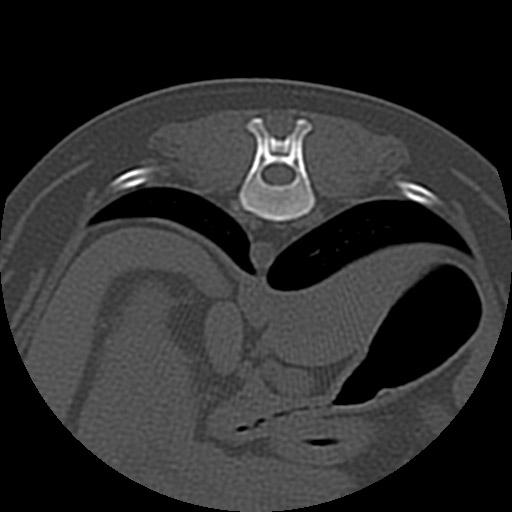

椎間板ヘルニア